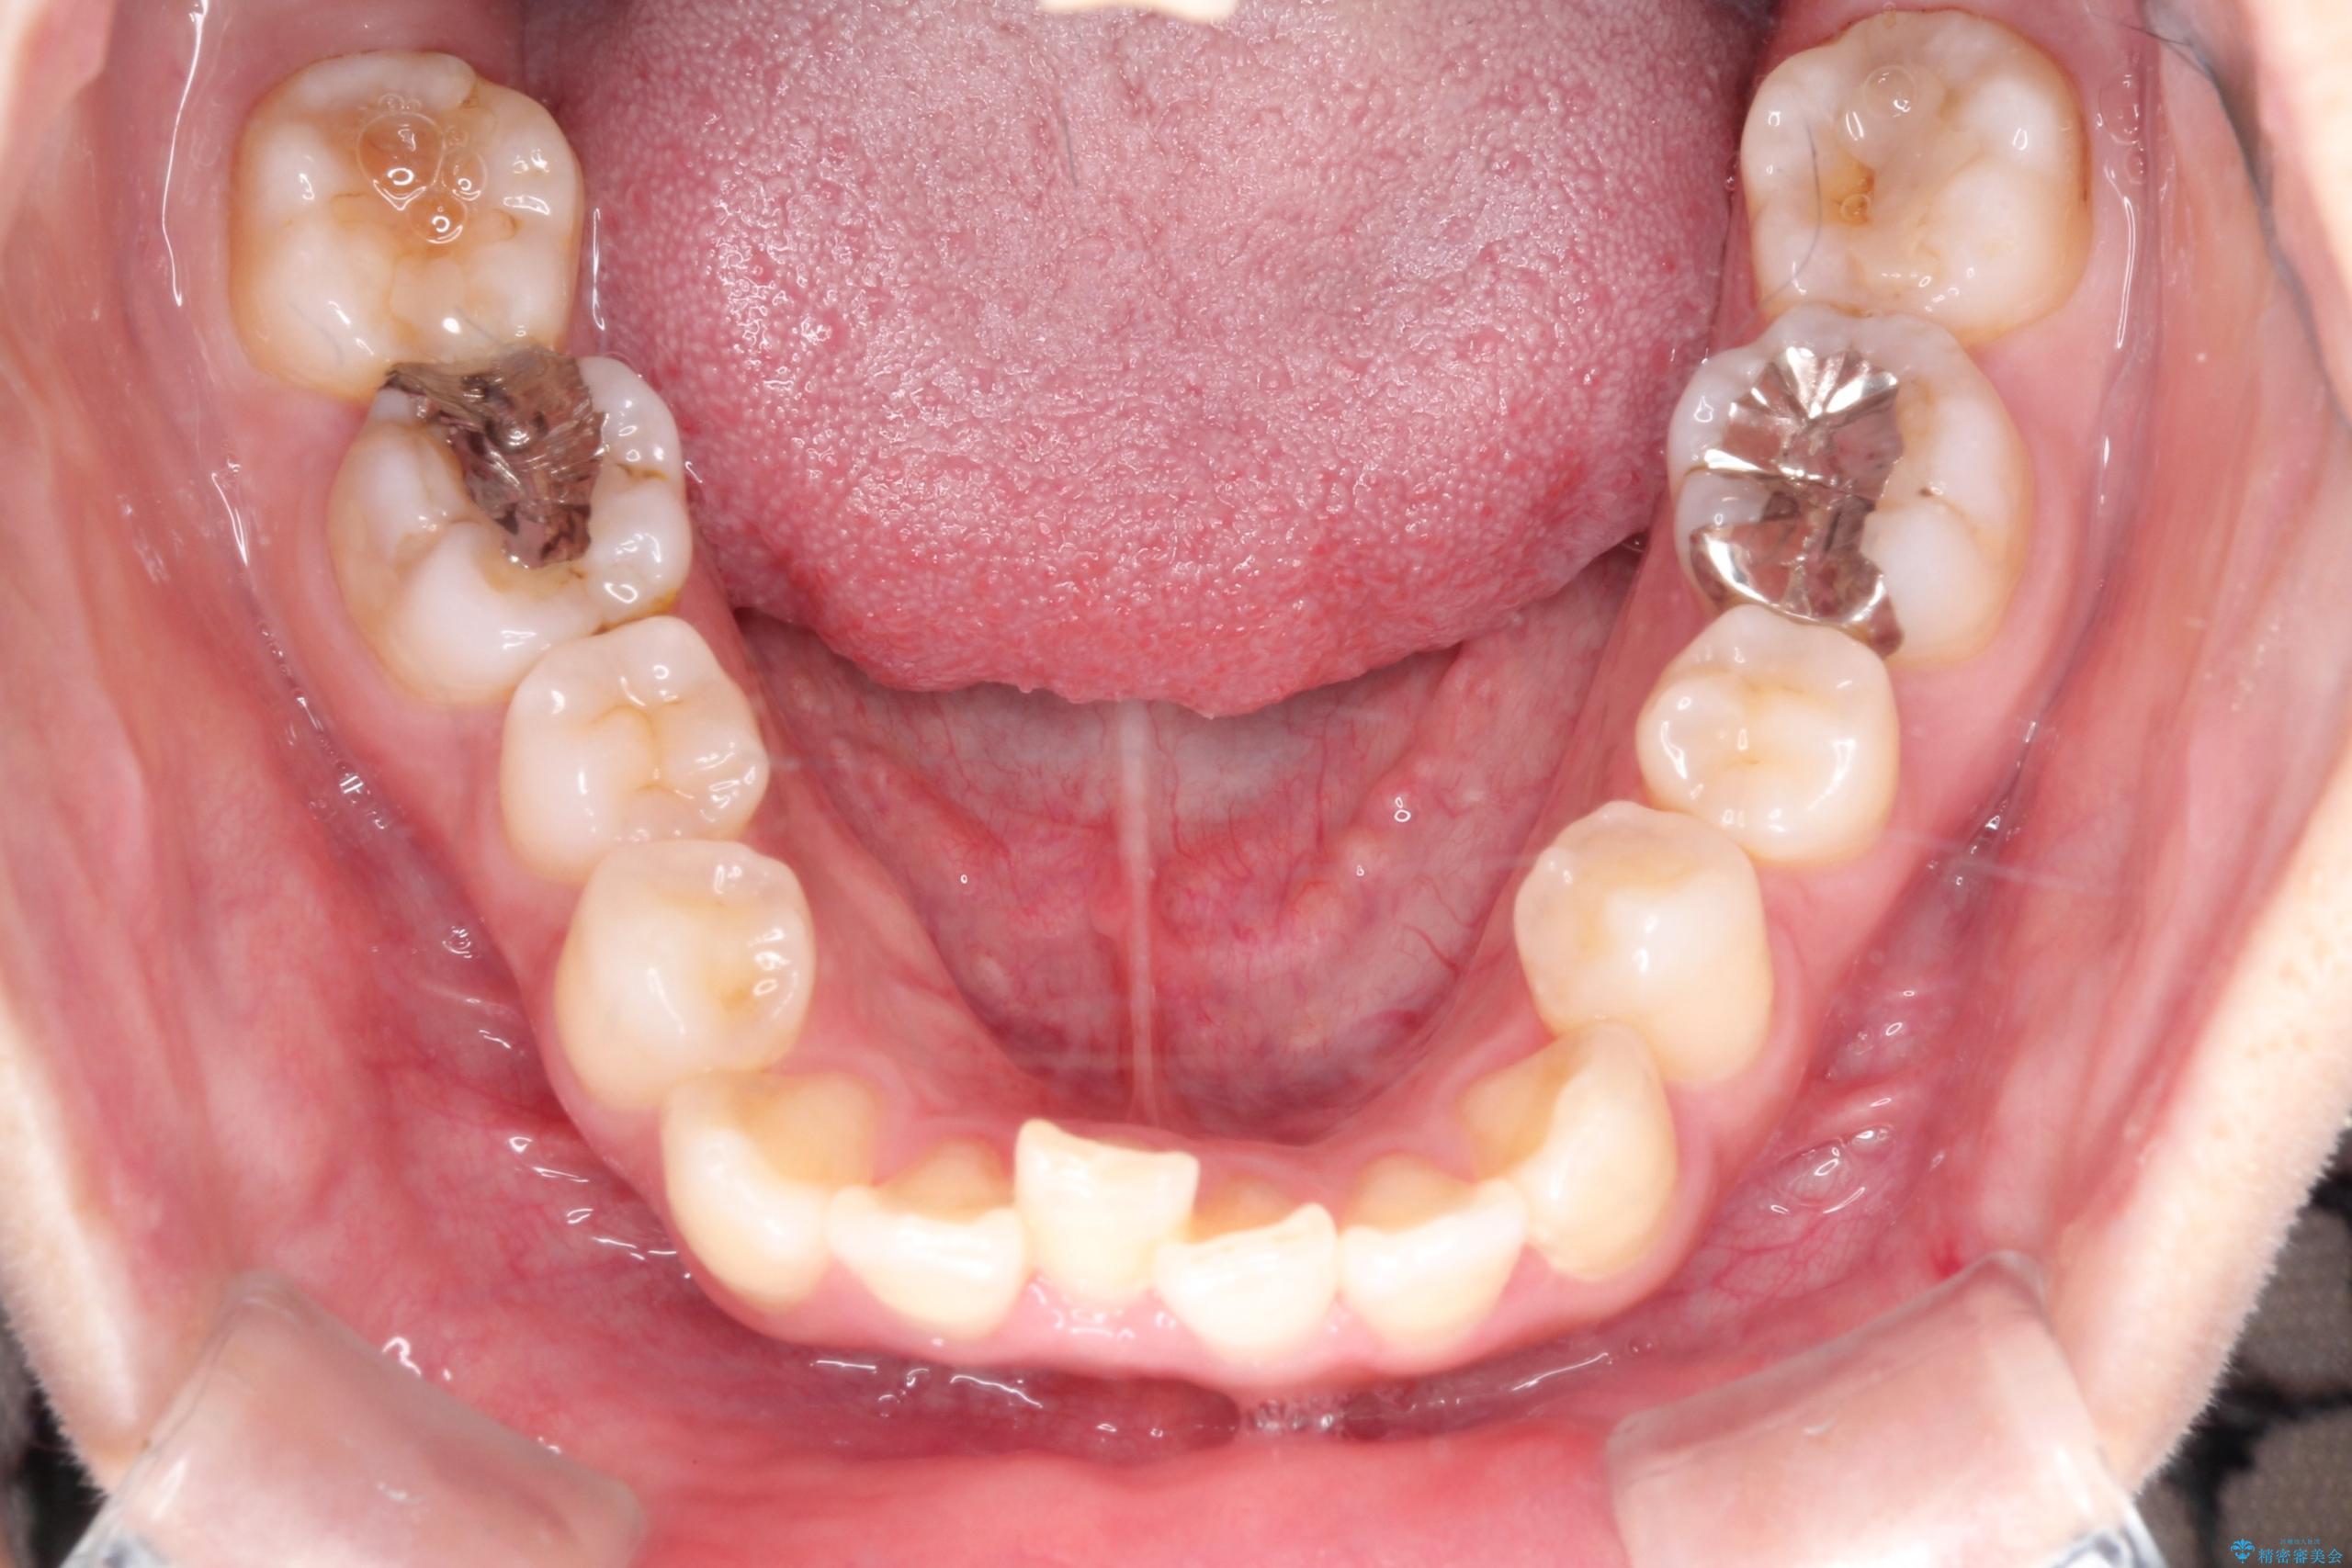

【ワイヤー矯正】口元を下げたい、下の歯の凹凸を無くしたい

- 主訴:口元を下げて前突感を無くしたい、下の歯の凹凸も無くしたい

右側第二小臼歯、左側第一小臼歯、下顎両側第一大臼歯を抜歯しワイヤ-矯正を行いました。

骨格的顎の変位を認めたため、顔貌に対しピッタリ上下の歯の正中を合わせることは難しいと説明し、上下左右計4本小臼歯を抜歯しワイヤー矯正治療を行いました。